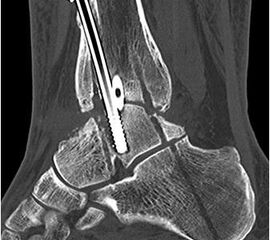

Implantation des Nagels und BV-Kontrolle (Video 5). Schließlich erfolgt die Verriegelung des Nagels über entsprechende Zielvorrichtungen. Bei einigen Nageltypen gibt es nageleigene Kompressionsmechanismen, die eine zusätzliche Drucksteigerung im Bereich der Arthrodeseflächen des ehemaligen oberen und unteren Sprunggelenkes erlauben (Video 6). Die abschließende BV-Kontrolle in beiden Ebenen sollte eine regelrechte Stellung der Arthrodese mit 90° - Stellung im Rückfuß, in der anderen Ebene mit einem Rückfußvalgus von ungefähr 5° zeigen.

• Primäre oder posttraumatische Arthrose des OSG und USG (Abbildung 1, Abbildung 2).

• Revision einer gescheiterten Fusion des OSG/ USG (Abbildung 3, Abbildung 4).

• Pseudarthrosen (Abbildung 5, Abbildung 6).